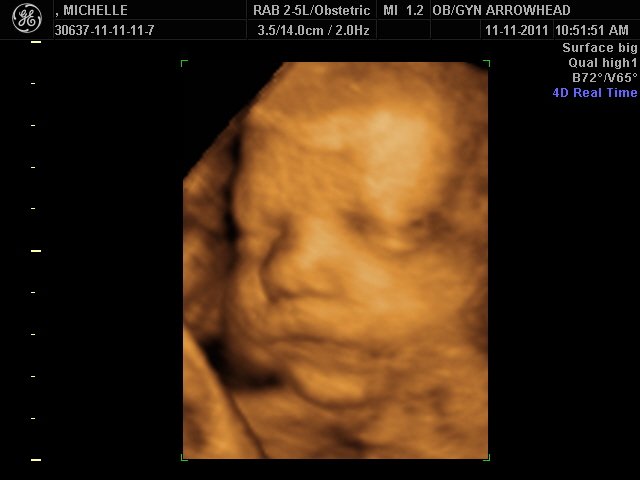

We offer complimentary 3D/4D Ultrasounds to all our OB patients around 30 weeks! The following photos are some examples of our work, shown with permission from our patients.